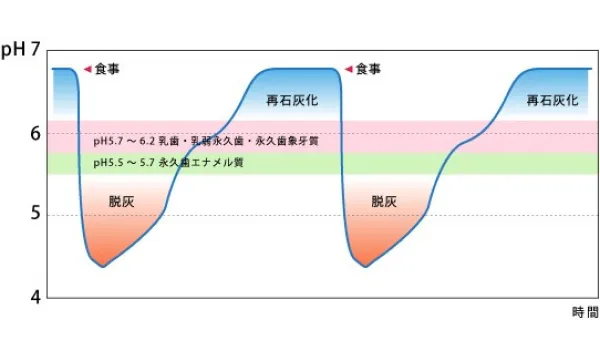

食事とpHの関係

食事をとると、2~3分でプラーク中のpH(ペーハー)は酸性に傾き、脱灰がはじまります。この脱灰の時間が長く続いたり、酸性度が強いほど虫歯の危険が増加します。唾液の力によって 約20~40分間でプラーク中のpHが上昇し、再石灰化がはじまります。